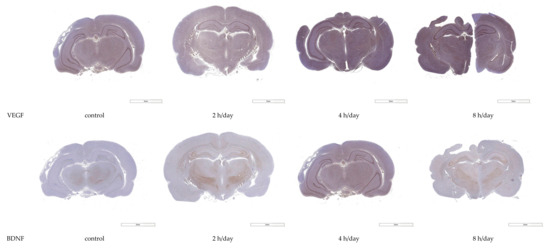

3.2. Western Blot and Immunohistochemistry

Western blot analyses and immunohistochemistry with antibodies to VEGF and BDNF were conducted for the hippocampal tissue after the rats had been kept in normal circumstances for five days. The reactivities of the VEGF protein were 44.63±5.28 in the control group, 55.30 ± 3.46 in the 2 h per day group, 62.93 ± 4.91 in the 4 h per day group, and 59.30 ± 1.82 in the 8 h per day group. The reactivities of the BDNF protein were 29.88 ± 2.02 in the control group, 34.11 ± 1.86 in the 2 h per day group, 33.52 ± 2.47 in the 4 h per day group, and 31.59 ± 2.16 in the 8 h per day group. The reactivities of the VEGF protein showed more reactivity in the 2 h per day, 4 h per day, and 8 h per day groups compared with the control group (p = 0.003). However, there was no reactivity for BDNF among the groups (p = 0.140) (Figure 5). Next, immunochemically stained tissues were quantified using the IHC image analysis toolbox developed based on Image J. The quantification of VEGF immunohistochemistry in the hippocampal area was shown as 1120.0 ± 117.7 in control group, 1455.5 ± 255.8 in the 2 h per day group, 1842.8 ± 135.0 in the 4 h per day group, and 1366.3 ± 399.1 in the 8 h per day group. The pixel of the VEGF positive DAB showed more in the 2 h per day and 4 h per day groups compared with the control group with one-way ANOVA with LSD post hoc test (p = 0.015). The quantification of BDNF immunohistochemistry in the hippocampal area was shown as 309.8 ± 186.0 in control group, 432.0 ± 191.9 in the 2 h per day group, 439.3 ± 135.0 in the 4 h per day group, and 542.5 ± 154.1 in the 8 h per day group. There was no significant difference among the groups with one-way ANOVA with LSD post hoc test (p = 0.326) (Figure 6).

Figure 5.

Western blot analysis of VEGF and BDNF expression. The VEGF protein was more reactive in the 2, 4, and 8 h per day groups compared with the control group (p = 0.003). However, expression of the BDNF protein showed no difference among the groups (p = 0.140). * p < 0.05 compared with control group.

Figure 6.

Immunohistochemistry for VEGF and BDNF expression and quantification of immunohistochemistry. Immunohistochemistry analyses of VEGF at hippocampal area revealed significantly greater immunoreactivity in the 2 and 4 h per day groups compared with the control group (p = 0.015). * p < 0.05 compared with control group.